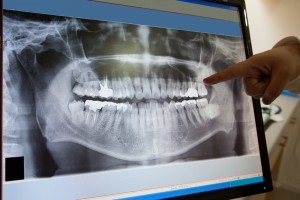

Digital X-rays

Digital X-rays use less radiation than traditional X-rays, and provide high-resolution images of your teeth and jaws. Because they provide highly-detailed images, digital X-rays are a vital tool for detecting early signs of oral cancer, tooth decay, and infection.